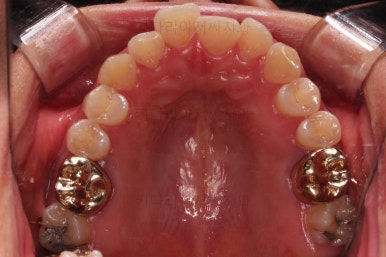

부산안면비대칭 첫 단꼐로 악궁확장 장치를 했어요.

비대칭이 있어서 한 것도 아니고, 공간이 부족해서 한 것도 아니에요.

비발치로 하고자 해서 한 것도 아니에요.

단순히 위아래의 조화가 안맞을 때 하는 것이 악궁확장이며 이번 환자분도 위아래의 조화가 안맞아서 악궁확장장치를 사용했고, 그 근거는 CT 분석을 통해서 이루어져요.

악궁확장 이후에 교정장치를 부착하고 치열을 가지런하게 해줘요.